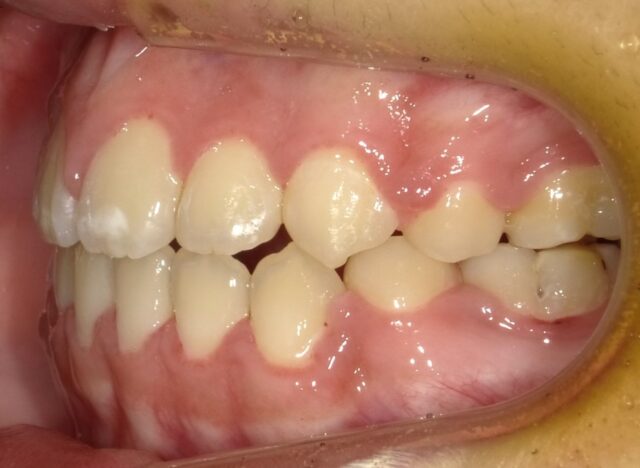

≪右側面観≫

2023年5月

2025年1月